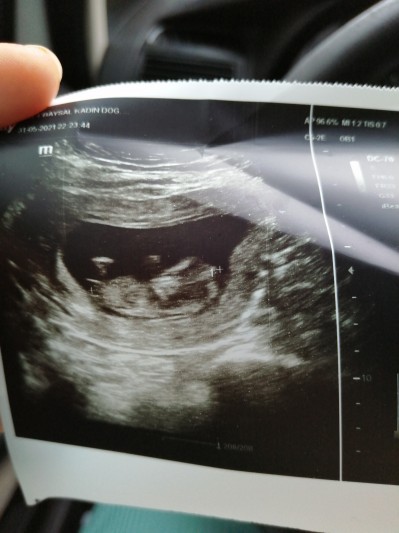

Ikili tarama için gitdim. Bugün doktorum bi şöyle bakti kaldırdı hemen birde cinsiyeti sordum 18 hafdada söylüyoruz dedi:( resime siz bakn tahminde bulanalım:)

Gebelik haftası 12